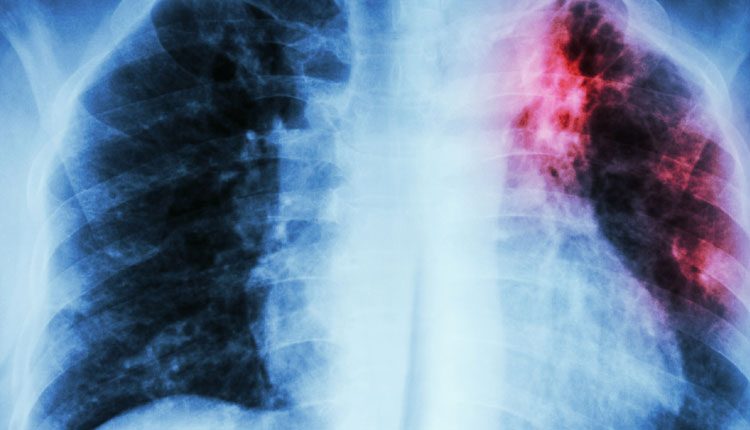

Tuberculosis | కరోనా మహమ్మారి నుంచి కోలుకున్న వారిలో చాలా మందిని అనేక అనారోగ్య సమస్యలు వెంటాడుతున్న విషయం తెలిసిందే. తాజాగా కర్ణాటకలో కొవిడ్ నుంచి కోలుకున్న 155 మందిలో టీబీ ( క్షయ వ్యాధి ) లక్షణాలు గుర్�